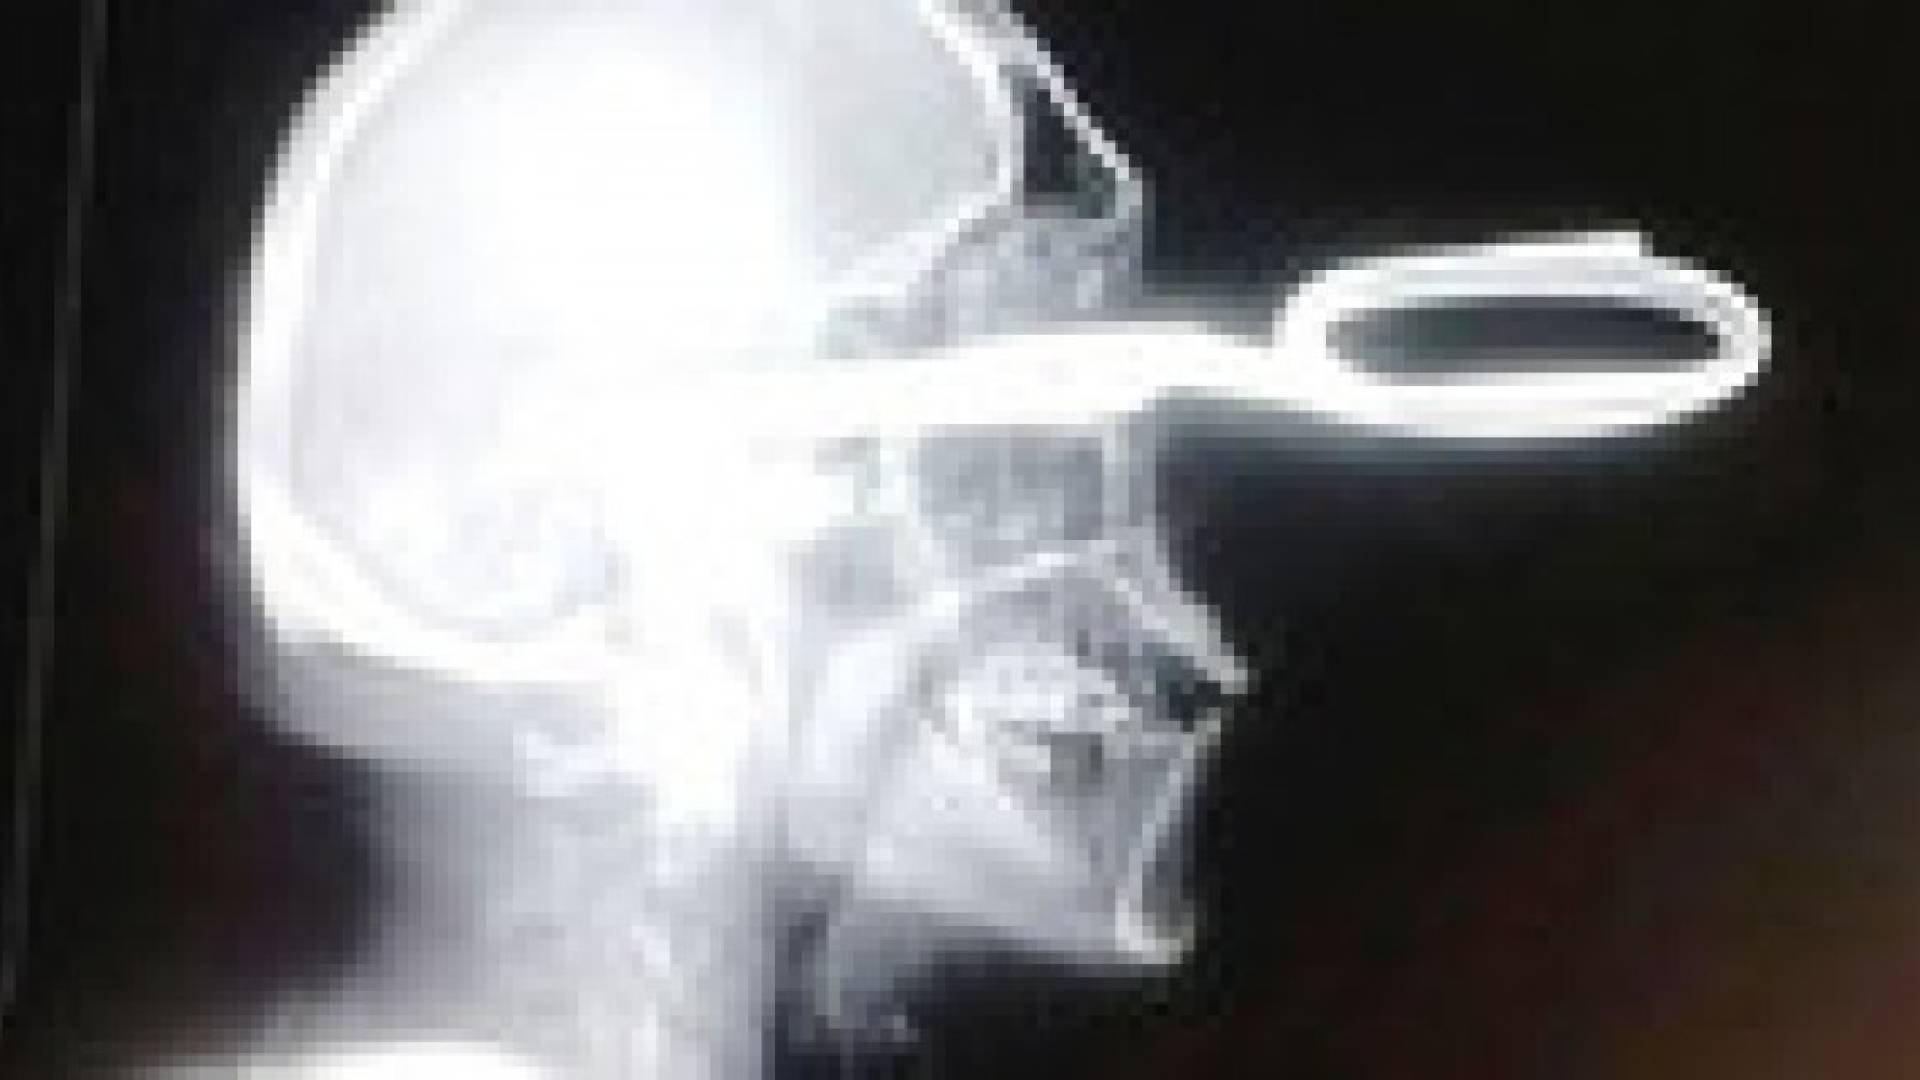

مكسيكي يزور مستشفى والمقص منغرز في رأسه

وكتبت صحيفة "ميرور" أن الرجل أتى الى المستشفى ماشيا على قدميه ومقص منغرز في رأسه، وليقول للطبيب أنه يواجه "مشكلة بسيطة" .

وفي التفاصيل، قال شهود العيان إن الرجل كان جالسا في البار مع اصدقائه عندما اقترب منه شخص مجهول فبدأ في إهانته. وكان تصرف الرجل هادئا حيث حاول تحويل النزاع إلى مجرد مزح بسيط. لكن المجهول اشتد غضبا، فسحب مقصا من جيبه واعتدى على الرجل غارزا المقص في رأسه ، ثم فر من البار.

ولحسن الحظ بقي الرجل على قيد الحياة لأن المقص لم يصب القسم الخلفي لدماغه.